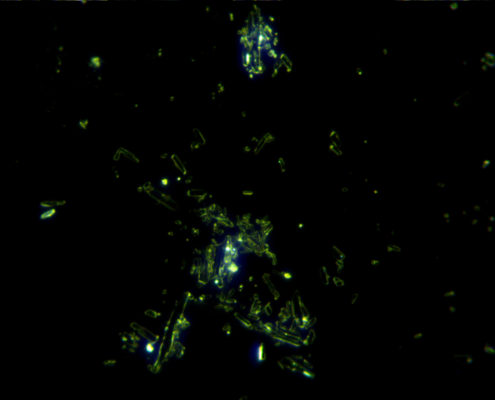

Darkfield analýza alebo aj analýza živej kvapky krvi v tmavom poli je mikroskopická technika, ktorá umožňuje screening komponentov krvi klienta v reálnom čase. Touto technikou je možné pozorovať javy, ktoré sa bežnými laboratórnymi metódami nezisťujú a preto je táto analýza vynikajúcim doplnkom k liečbe. Živú kvapku krvi je možné takto pozorovať len 10 – 20 minút.

Analýza je takmer bezbolestná, kvapka sa odoberie z prsta a dá sa na podložné sklíčko, zľahka sa prekryje krycím sklíčkom. Obraz krvi je snímaný kamerou do PC, čo umožňuje klientovi vidieť to isté čo vidí terapeut pod mikroskopom. Klient vidí jednotlivé krvinky a všetko čo sa v krvnej plazme deje v dostatočnej veľkosti. Výsledné zväčšenie je 1 000 – 2 000×. Pozorovaním kvapky krvi sledujeme prítomnosť, kvalitu a stav rôznych žiadúcich i nežiadúcich krvných zložiek, čo nám mnohé napovie o zdravotnom stave, aj keď nevedie k pomenovaniu presnej medicínskej diagnózy. Z každého pozorovania vytvárame fotografie, ktoré sú ukladané do karty klienta pre porovnanie pri následnej kontrole.

- prítomnosť nežiadúcich mikroorganizmov

- krvné mykózy